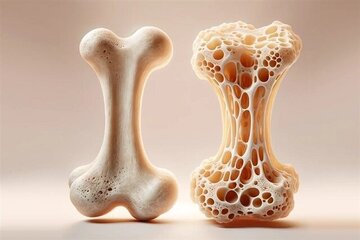

ویتامین A برای بینایی، سلامت پوست، سیستم ایمنی و سلامت استخوان ضروری است.